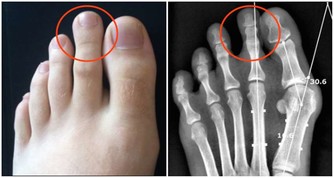

七、腎臟排毒

腎臟是人體最重要的排毒器官,不僅能過濾掉血液中的毒素並使其通過尿液排出體外,還起著保持人體水分和鉀鈉平衡的作用,控制著和許多排毒過程相關的體液循環。尿液中毒素很多,若不及時排出,會被重新吸收進入血液,危害全身健康。

最適合腎臟排毒的時間是早晨5點~7點。身體經過一夜的修復,體液循環代謝的毒素都聚集在腎臟。

【排毒措施】

1、充分飲水。每天一定要喝8杯水。水是最好的排毒載體,充足的水分不僅可稀釋體液中的毒素,還能促進腎臟的新陳代謝,將更多毒素排出體外。特別建議每天清晨空腹喝一杯溫開水,最好是生機果蔬汁。

2、不要憋尿。尿液中毒素很多,若不及時排出,會被人體重新吸收。

3、少喝甜飲料。甜飲料不等於水,喝多了會使身體攝取大量的糖分和熱量,對身體沒有好處。

4、多吃黃瓜、冬瓜、西瓜、櫻桃等蔬果有助於腎臟排毒。山藥、黑豆都是補腎的食物。經常吃山藥、黑豆可增強腎臟的排毒功能。